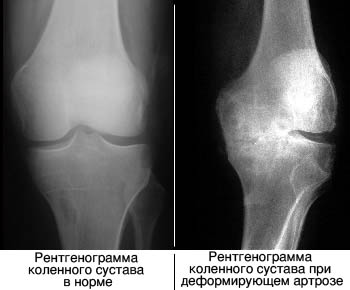

Диагноз можно установить после проведения рентгенографии пораженного сустава. Также возможно использование ультразвукового исследования для обнаружения воспалительных процессов в суставах и окружающих тканях.